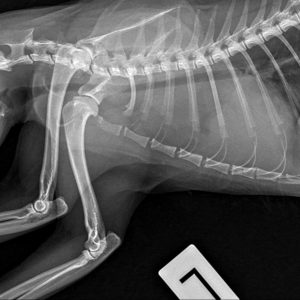

Zawiozłem ją z tego powodu do weterynarza. Została przeprowadzona diagnostyka i niestety, ten dzień stał się dla niej wyrokiem. Dla nas wszystkich. Małpeczka jest ciężko chora.Wykryto u Niej zmianę o charakterze guza. W celu potwierdzenia diagnozy należy przeprowadzić badanie tomografem komputerowym. Następnie powinno się wykonać torakotomię zwiadowczą z ewentualnym usunięciem zmiany lub pobraniem próbek do badania histopatologicznego. Koszt przeprowadzenia opisywanych procedur jest wysoki: 6 tysięcy zł.

Koszty te dla mnie obecnie są zbyt duże i na daną chwilę nie mam odpowiedniej kwoty. Operacja, tomograf, dalsze leczenie, dojazdy- przerastają moje możliwości. Dlatego proszę Was o wsparcie. W tym przypadku liczy się czas, czym prędzej uda się przeprowadzić operację, tym większe będą jej szanse na przeżycie i powrót do zdrowia. Zamieszczam zdjęcia rtg Małpeczki i opis badań.”